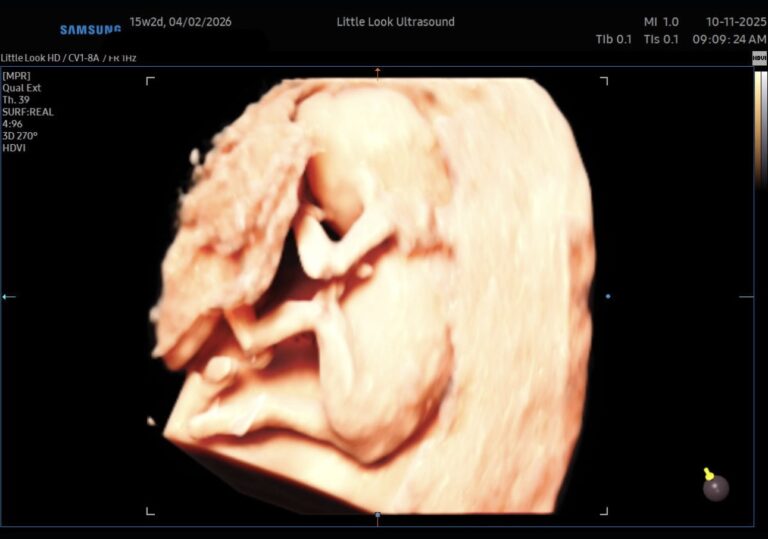

A Peek Inside: 3D/4D Ultrasound at 15 / 16 Weeks in Southern NH Pregnancy is full of “firsts” — first heartbeat, first fluttering kicks, first trimester checkups. For many parents, one of the most magical moments is seeing baby in 3D or 4D ultrasound. If you’re around 15 weeks along and considering a 3D/4D scan (especially…

What Do Babies Look Like in the Womb? A Guide to Every Stage of Pregnancy NH MAExpectant parents in New Hampshire and Massachusetts often wonder what their little one looks like before birth. Thanks to the advancements in 3D ultrasounds, families can now see their baby’s development more clearly than ever. From those first tiny features to the moment they’re ready to enter the world, here’s a look at what your baby looks like…

The Magic of 3D Ultrasound Technology: What You Need to KnowPregnancy is a journey filled with anticipation, excitement, and countless questions. One of the most cherished milestones for many expectant parents is seeing their baby on an ultrasound screen. With advances in imaging technology, 3D ultrasound has become a popular choice for families who want a more detailed and memorable view of their little one….